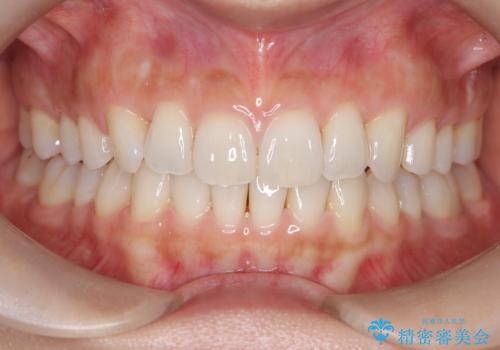

【インビザライン】前歯のねじれを治したい

- 前歯のガタガタを主訴に来院されました。

叢生の量は軽度でしたが臼歯の遠心移動を行い、インビザラインにて治療をしました。

叢生の改善に必要なスペースは遠心移動やIPRで作ることが可能です。今回は遠心移動をメインにスペースを作って叢生の改善を行いました。